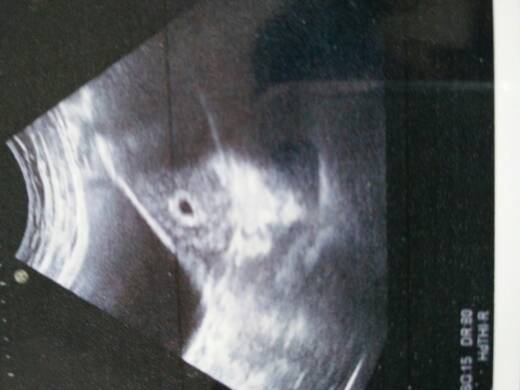

有经验的宝妈看看我的是位公子还是千金???谢谢 有经验的宝妈看看我的是位公子还是千金???谢谢 点击展开 虎虎逗逗 2015-05-02 11:11 为您推荐: 其他回答 对啊,,,, 爱丽&宝贝 2015-05-02 23:09 你bc单子上有没有数据啊看看 188*****978_po5n 2015-05-02 19:49 应该是女宝 如果v没有伱 2015-05-02 18:43 嘿嘿看不懂 爱丽&宝贝 2015-05-02 16:02 看不懂哦! 海绵宝宝_qi1O 2015-05-02 14:35 加载更多 相关问题 宝好们帮我看下是公子还是千金! 哪位宝妈帮我看看我的最后一次月经的时间啊!帮我算算吧!急急! 宝妈们!看看我的是男宝宝不??